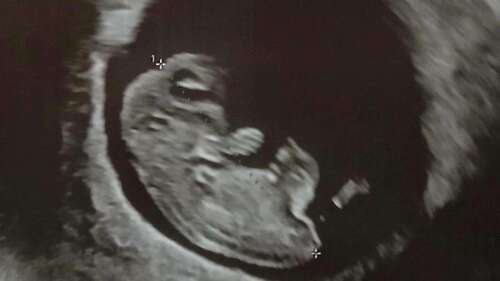

Hallöchen, ich war am Motto da, bei 13+3, und es war ganz toll :) die NIPT Ergebnisse waren alle unauffällig, auch die große Untersuchung hat ein quietschfideles Mädchen gezeigt 💕 Es war so beeindruckend ♥️